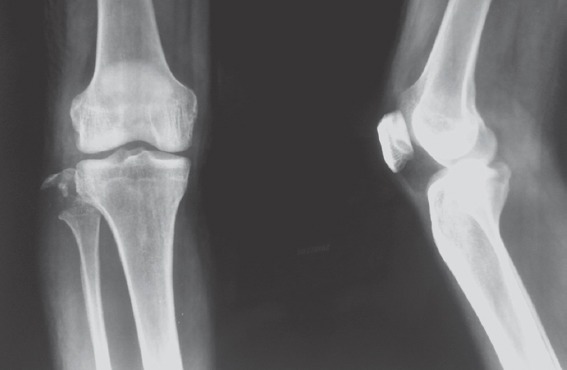

Figure 1.

Pre-operative X-ray shows avulsion fracture of the fibular head without dislocation of the knee joint.

Anteroposterior view of injured knee under varus stress shows opening of lateral joint line.